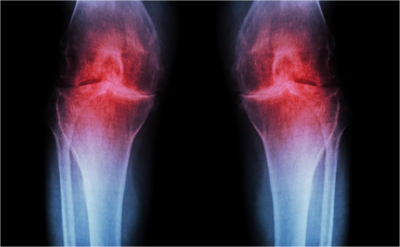

المفصل هو المكان الذي تلتقي فيه عظمتان، وتُغطى نهايات هذه العظام بأنسجة واقية تسمى الغضاريف. مع حدوث خشونة المفاصل، تنهار هذه الغضاريف، مما يتسبب في احتكاك العظام في المفصل، مُسبباً ألماً وصلابة للمفصل وأعراض أخرى.

خشونة المفاصل والغضاريف

الغضروف عبارة عن مادة مطاطية صلبة لكنها مرنة وأكثر ليونة من العظام. وتتمثل مهمتها في حماية نهايات وأطراف العظام داخل المفصل، والسماح لهم بالتحرك بسهولة ضد بعضهم البعض وذلك بمنع احتكاكهم.

عندما يبدأ الغضروف في الانهيار، تُصبح هذه الأسطح عظمية وخشنة. وبالتالي يتسبب في حدوث الألم داخل المفصل، وتهيُّج في الأنسجة المحيطة. تكمن المشكلة في أن الغضروف التالف لا يستطيع إصلاح نفسه. وذلك لأن الغضروف لا يحتوي على أي أوعية دموية ولا أنوية تُمكّنه من الانقسام.

عندما يختفي الغضروف تماماً، يختفي المخزن المؤقت المُبطِّن الذي يوفره لحماية العظام، مما يتيح ملامسة العظام. لبعضها البعض والبدء في التآكل.

خشونة مفاصل الرُكبتين

مثل خشونة مفصل الورك، يمكن أن تحدث الخشونة في رُكبة واحدة أو كلا الرُكبتين.